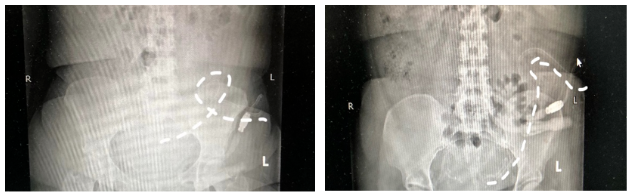

60岁的老李是一位刚刚开始腹膜透析的肾友,最近给腹透中心的医务人员打来电话说,平时超滤有200多,最近开始出现了负数,近期体重开始增加。接到电话,医务人员把老李约到门诊,仔细询问之下,发现他透析后食欲明显增加,很爱吃肉,不爱吃蔬菜,排便约3天一次,质偏干,平时不爱运动。在立卧位腹平片的检查中,医务人员发现老李出现了“飘管”,腹腔中的那根软软的腹透管不在自由下垂,而是“舞动”起来,这是腹透液引流不畅的原因。随后,医疗团队为他制定了一套饮食生活方案。

2周后,腹透中心医疗团队再次与老李取得了联系,按照建议,老李饮食上荤素搭配,增加运动,按时排便,腹透液逐渐排出顺畅。老李再次做了腹平片,发现这根舞动的导管已经悄悄下垂,回到了该有的位置。